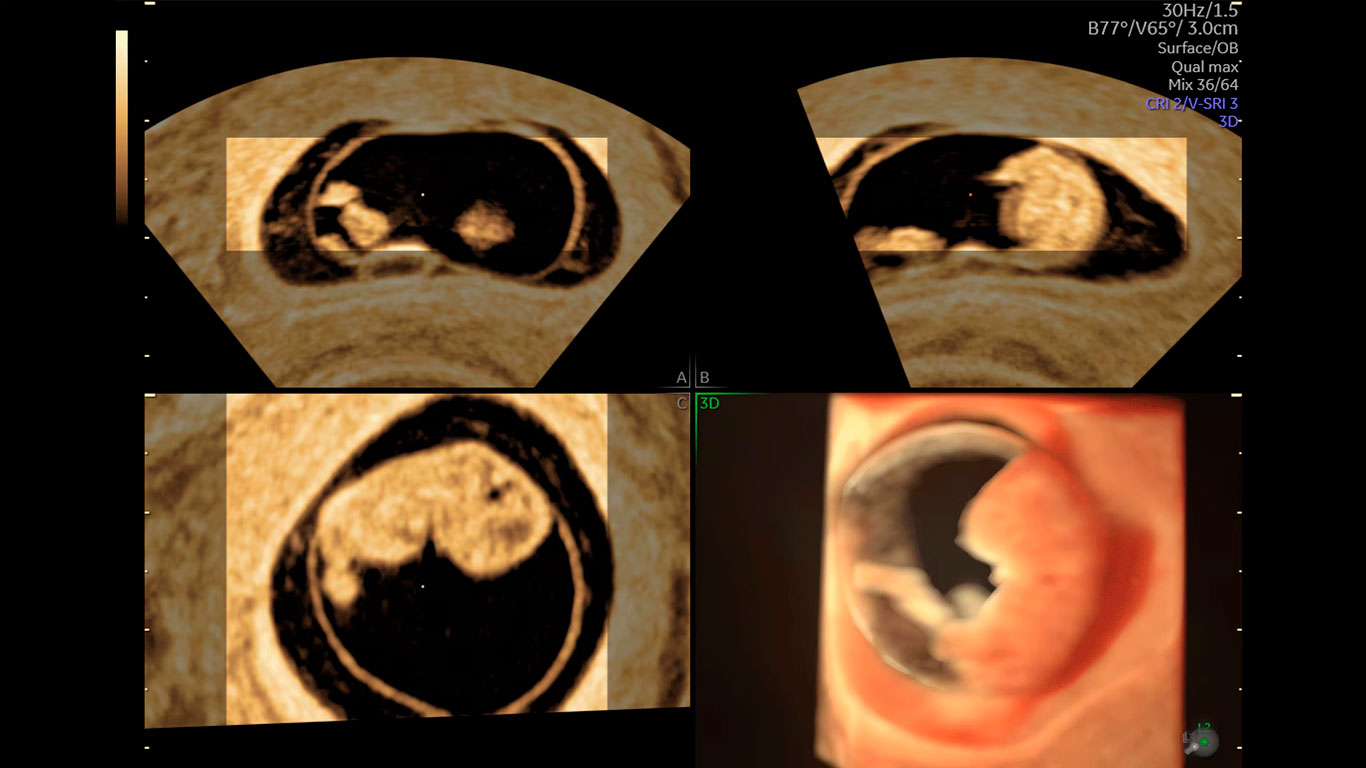

El sistema Voluson Expert 20 le ayudará a responder a cuestiones relevantes con imágenes de última generación para agilizar la evaluación y el diagnóstico. Ahorre un tiempo valioso con la inteligencia artificial (IA) y las herramientas de automatización que ayudan a descubrir nuevas eficiencias en cada paso.

“Estos equipos tienen múltiples recursos que realmente me permiten, no solo cumplir con las expectativas diagnósticas de los colegas, sino siempre ir un poco más allá”.

Dr. Juan Fajardo

Radiólogo

«Los avances que se han conseguido en los Voluson en los últimos años son muy elevados y eso permite unos diagnósticos precisos y un manejo más amigable para el profesional».

Dr. Eduard Gratacós

Ginecobstetra